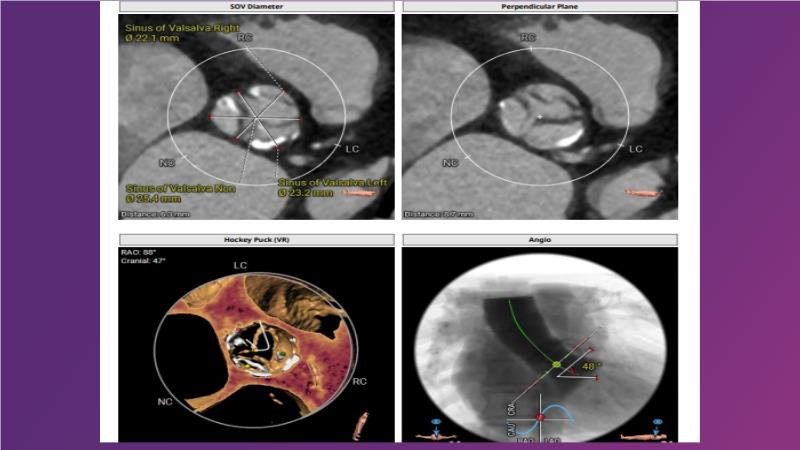

Gain expertise in selecting the appropriate TAVI device for achieving stable deployment in a 90-degree horizontal aorta. Discover techniques for ensuring smooth deliverability, particularly when navigating through tight and tortuous anatomies. Additionally, learn strategies to prepare for future coronary access, irrespective of the height of the left or right coronaries.

• To learn how to select your TAVI device in order to achieve stable deployment in 90 degrees horizontal aorta

• To be ready for future coronary access regardless of the height of left or right coronaries